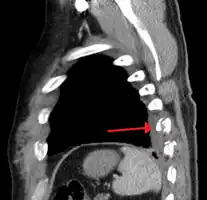

Right sided pneumothorax and rib fractures

Two broken ribs as seen on parasagittal CT

Plain X-rays often pick up displaced fractures but often miss undisplaced fractures.[13] CT scanning is generally able to pick up both types of fractures.[13]